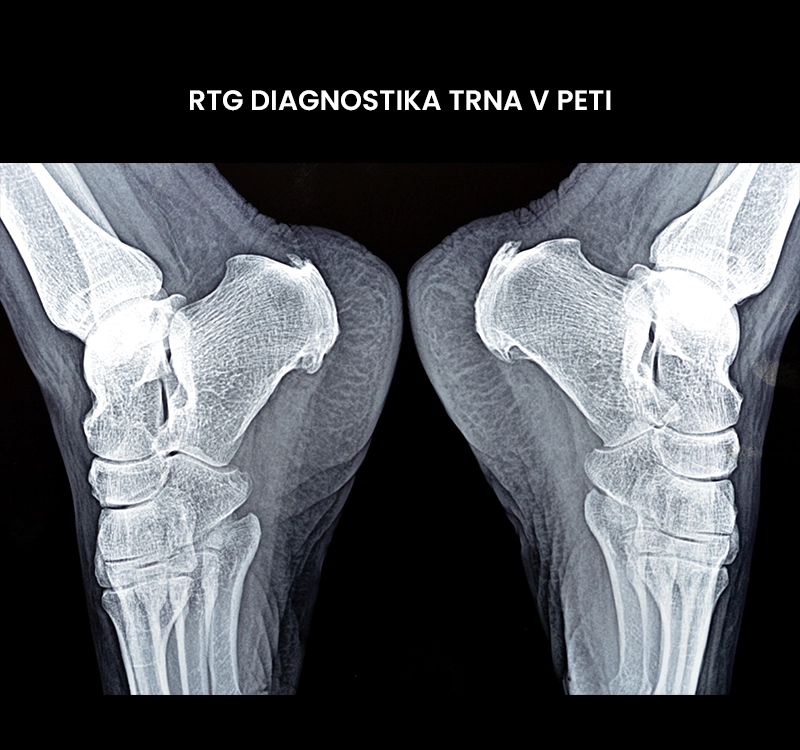

Kako diagnosticiramo trn v peti (diagnostični pregled)?

Trn v peti diagnosticira zdravnik na podlagi anamneze, kliničnega pregleda in slikovne diagnostike. Fizioterapevt v okviru diagnostičnega pregleda potrdi verjetnost prisotnosti trna v peti.

• Slikovna diagnostika v obliki rentgenskega slikanja (RTG) in magnetne resonance (MRI) se uporablja za opredelitev natančne diagnoze. RTG se uporablja za ugotavljanje prisotnosti, velikosti in mesta trna. MRI se uporablja le v redkih primerih za prikaz morebitnih poškodb mehkih tkiv.

Trn v peti Trn v peti RTG diagnostika trna v peti

RTG diagnostika trna v peti